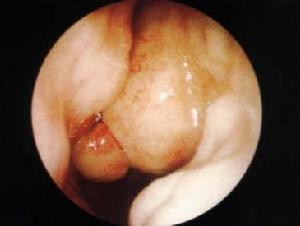

2.腫瘤位於枕骨大孔前方時中國外均採用經口腔入路。此入路術後易合併腦脊液漏,故切除腫瘤後應嚴密修補硬腦膜。